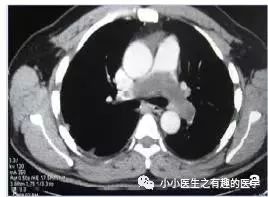

女性,33岁,反复劳累后呼吸困难5月,胸膜炎性胸痛,伴有咳嗽,以肺栓塞可能收入院。

A 33-year-old female with a 5 month history of recurrent episodes of exertional dyspnoea, pleuritic chest pain and an urge to cough was referred to hospital with the tentative diagnosis of pulmonary embolism.

看CT,左肺动脉血栓了。患者结局呢?

遗体解剖发现肺动脉肿块,延伸至右心房。病理:原发性肺动脉绒毛膜癌。

At autopsy, a tumour was found occluding the left pulmonary artery extending into the right atrium. Histological evaluation showed a primary choriocarcinoma.

这不是癌栓,这是肺动脉的肿瘤。